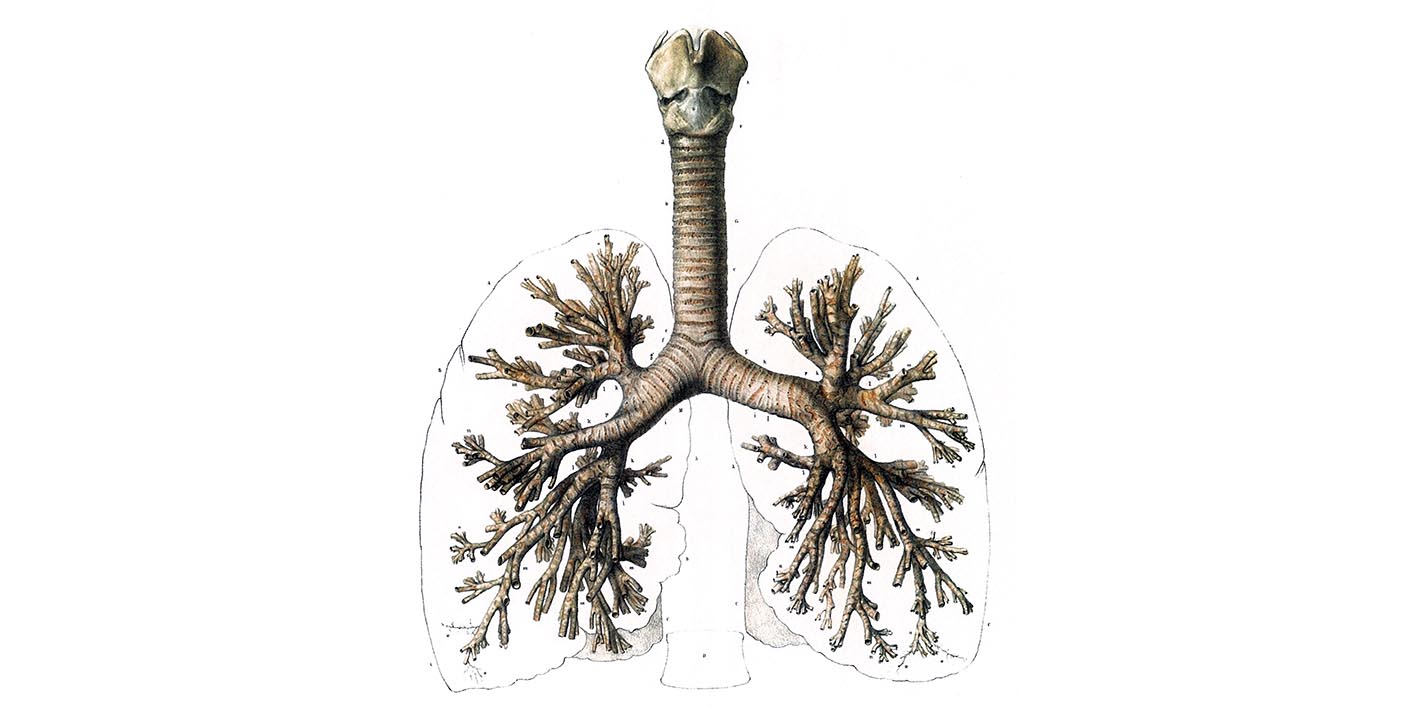

気管の壁には15~20個の馬蹄形の気管軟骨があり、後壁は軟骨を欠き、平滑筋を含む膜性壁が存在する。気管支もその構造は肺門までは気管とまったく同じで、気管軟骨の間の輪間部は強靱な結合組織性の輪状靱帯からなり、内面は杯細胞を含む多列線毛上皮からなる粘膜で気管腺が存在する。(p.10 上皮組織の分類, p.65 気管と気管支)